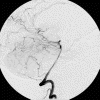

A diagnostic angiography was done during his hospitalization and yielded the following images.